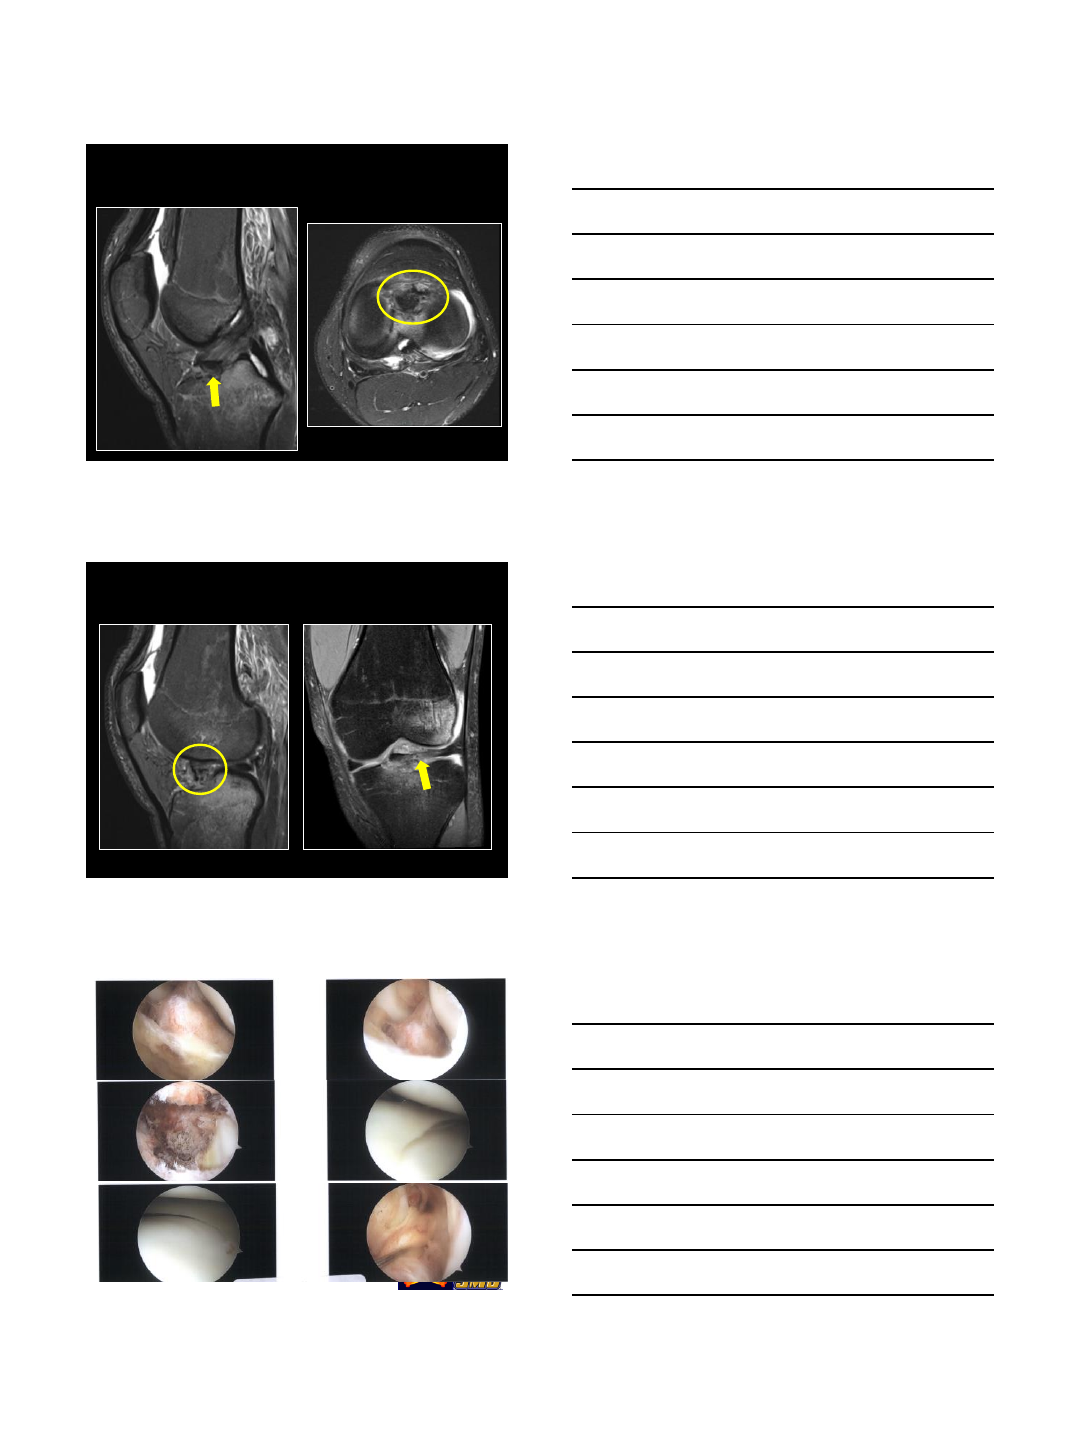

47 year-old female with medial knee pain. Prior

history of meniscal root re-attachment.

Radial tear

• Radial split at the post horn root junction MM. “Ghost sign”

•Subacute subchondral medial plateau fracture with mild bone plate

depression and focal area of devitalized bone

One year later